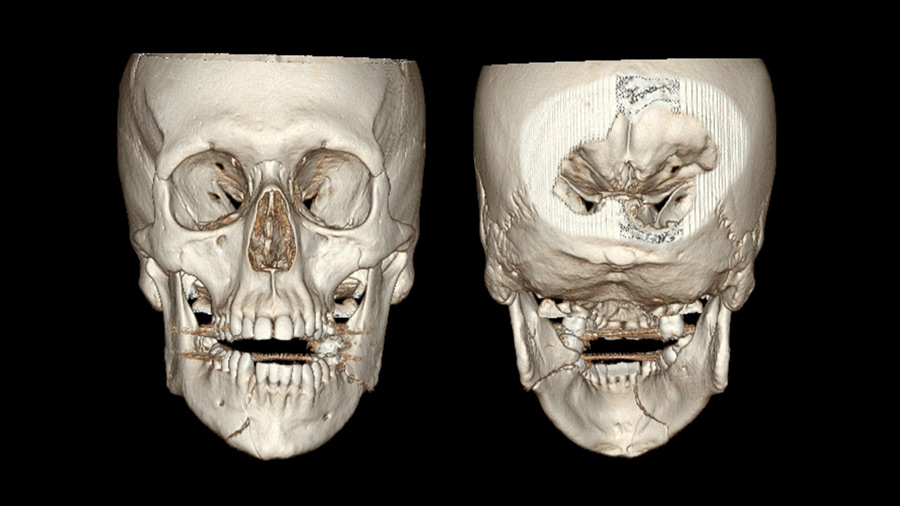

But no grossly loose teeth. Maxilla stable, the rest of the neurovascular and craniofacial examination is completely normal. What you're looking at is an mandible fracture. How did you describe this - this fracture pattern that you see in front of you?

Dr. Susarla: As you know, the first is to think is the fracture pattern concordant with the patient's clinical symptoms. The description that you provided about paresthesia and kind of the lower facial distribution that would be expected in a patient with mandibular injury because of the transit of the inferior alveolar nerve. And also coincident with the description is that gingival laceration between the right lateral incisor and the canine.

The imaging shows a right parasymphyseal fracture and a left mandibular angled fracture. And the concordance of the imaging findings with the clinical exam should be reassuring to you. Sometimes when there's a discrepancy between the two, you have to reconcile that. And one of the most important points about mandible fractures that I've learned over time and we try to stress to our own trainees is when you see a patient with what is presumed a unilateral mandible fracture, it's your job to rule out a bilateral or counter coup injury because they often occur in pairs, as you see in this case.

Now, this fracture orientation at the angle is favorable because the angulation of the fracture runs perpendicular to the masseter muscle, so you can see on the imaging that the fracture is generally nondisplaced. A subtle finding on the imaging, which is really important, is that there is a tooth in the way of the fracture which appears to be outside of the arch alignment.